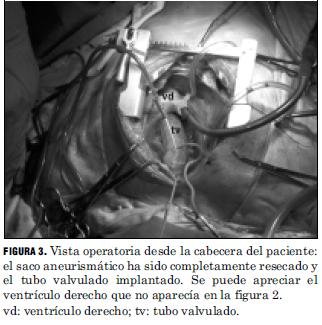

Se realizó infusión de cardioplegia blanca extracelular (7) por ambos ostium coronarios a la dosis de 30 ml/kg la cual se repitió cada 30 minutos. Resección de la totalidad de la pared del aneurisma y extracción de ambos ostium coronarios con un collarete de pared aórtica y valvulectomía aórtica. Colocación de tubo valvulado Medtronic N° 21 de Dacron con prótesis monodisco fijada con puntos en U apoyados en teflón de Ethibon 2-0.

Anastomosis de ambos ostium coronarios con su collarete de pared aórtica con surget de prolene 6-0 y finalmente anastomosis distal entre el tubo de Dacron y la porción de aorta ascendente transeccionada inmediatamente por debajo del nacimiento del tronco arterial braquiocefálico (Fig. 3).